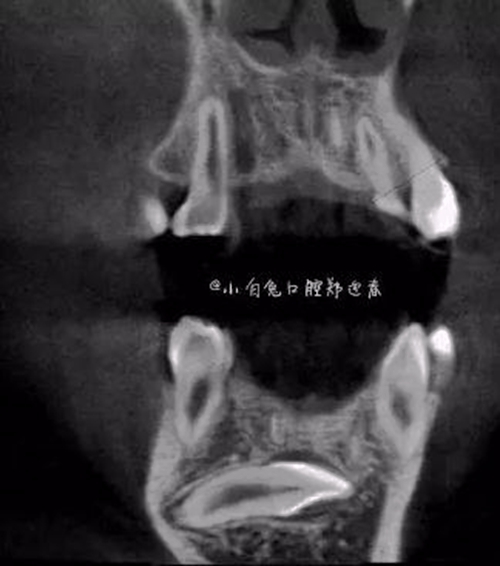

本案:患兒,女,14歲,因牙齒矯正來院,檢查見83滯留,43未見萌出,拍片發(fā)現(xiàn):43埋伏阻生于31、41、42根尖下方,按照正畸診療計劃,擬行43拔除術(shù)。

CBCT顯示